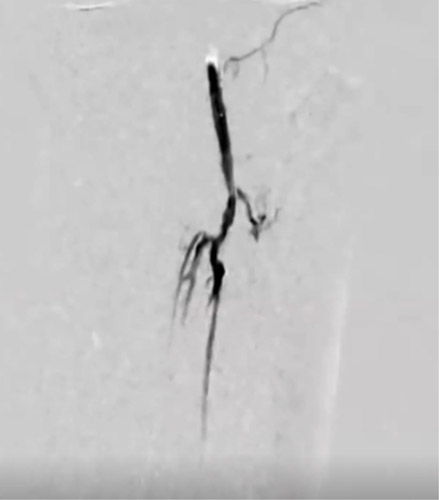

DAは閉塞していたが内腔はあるので穿刺を検討したが、難しいと判断しPTAを穿刺した。PTA経由でATAにレトログレードアプローチを行いDAからシースを挿入するため、1gワイヤーを進めたがATA(Anterior Tibial Artery)方向へワイヤリング出来ないため、Zizai™をPOP方向へ進め造影した(図3)。ATA入口部は狭窄しており、更に末梢は閉塞していることを確認した。ATA入口部へワイヤー通過に成功し急峻な角度ではあったがZizai™を追従させ(図4)、ATAは閉塞血管でありワイヤールートはSubでも良いと判断しワイヤーナックルにて末梢まで進めた。DAを18G針で穿刺をしワイヤーランデブーに成功した(図5)。その後、DAに4Frシースを挿入し、2.5㎜径バルーンでATAを拡張したあと、PTAのワイヤーとZizai™を抜去後にアプローチサイトの止血を行い、ATAの4Frシースからガイディングシースへ入れ替えを行った。

症例の流れ:ATAからSFAへのアプローチ